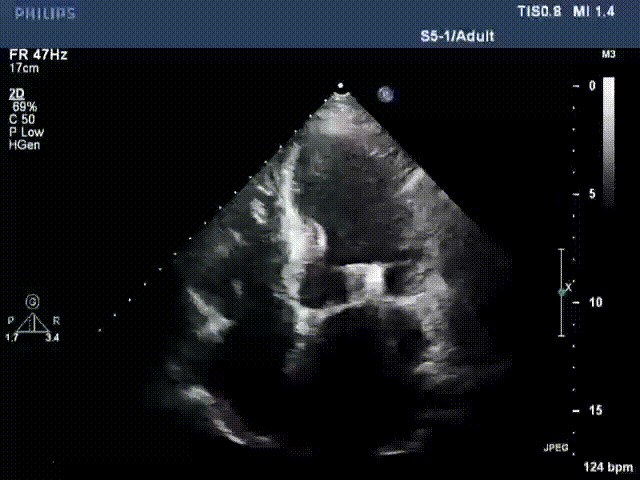

術(shù)前超聲提示二尖瓣重度反流

術(shù)后超聲顯示二尖瓣反流消失,瓣膜夾穩(wěn)定

出院前隨訪超聲

接受治療的是一例器質(zhì)性重度二尖瓣反流(DMR)患者,主訴“反復(fù)活動后胸悶,氣促3年余”。術(shù)前超聲顯示,雙房增大,二尖瓣脫垂伴重度反流,輕度三尖瓣反流,輕度肺高壓,升主動脈增寬。手術(shù)經(jīng)股靜脈-房間隔入路,采用全身麻醉插管,在TEE和DSA引導(dǎo)下完成房間隔穿刺。置入JensClip瓣膜夾系統(tǒng)后,在左房調(diào)整瓣膜夾的位置和軸向,后進(jìn)入左室,在TEE引導(dǎo)下捕捉二尖瓣前后瓣葉,并關(guān)閉瓣膜夾。經(jīng)TEE反復(fù)確認(rèn)手術(shù)效果后最終鎖定并釋放瓣膜夾。術(shù)后即刻超聲顯示瓣膜夾位置穩(wěn)定,功能良好,術(shù)前二尖瓣反流4+,術(shù)后0反流,肺靜脈逆流和左房壓都顯著好轉(zhuǎn),手術(shù)圓滿成功(以上數(shù)據(jù)都來源于醫(yī)院的臨床記錄)。術(shù)后患者狀態(tài)良好,目前已安排出院。